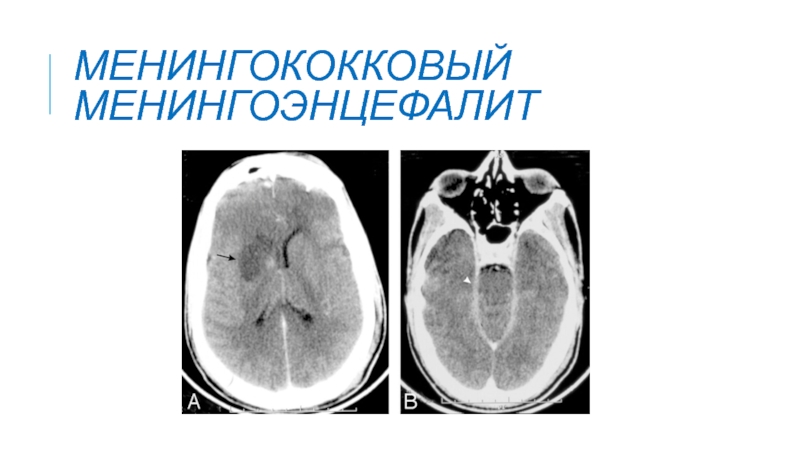

Слайд 26Менингококковый менингоэнцефалит

Менингококковый менингоэнцефалит